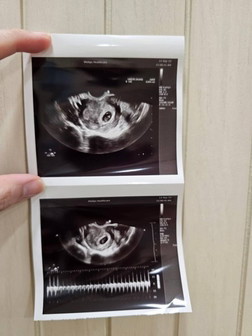

กี่weekถึงเจอตัวเด็กในครรภ์

ของแม่ๆกี่Weekถึงเจอเด็กในครรภ์คะ

ฝากครรภ์น้องตั้งแต่ weeks ที่ 8 ค่ะ ครั้งแรกไปพบหมอใช้เจาะเลือดผลตั้งครรภ์จริง ครั้งที่ 2 พบหมอให้อัตราซาวน์ทางช่องคลอดพบน้องแล้วค่ะ เลยฝากครรภ์กับคุณหมอเลย

7 w 3 d ซาวน์หน้าท้องเจอน้องแล้วค่ะ แต่เล็กมากๆเจอยากมากๆเลย

ซาวหน้าท้องเจอตัวอ่อนพร้อมเสัยงหัวใจตอน6+4จ้า

เราเจอตอน 7 +5 day ค่ะ ทางช่องคลอดนะคะ

บ้านนี้ท้องแรกเจอตัวน้องตอน10w

เราซาวด์หน้าท้อง เจอตอน 7w ค่ะ

ของเราเจอตอน6วีคค่ะ

8 weekค่ะ ทางช่องคลอด

บ้านนี้เจอ6w